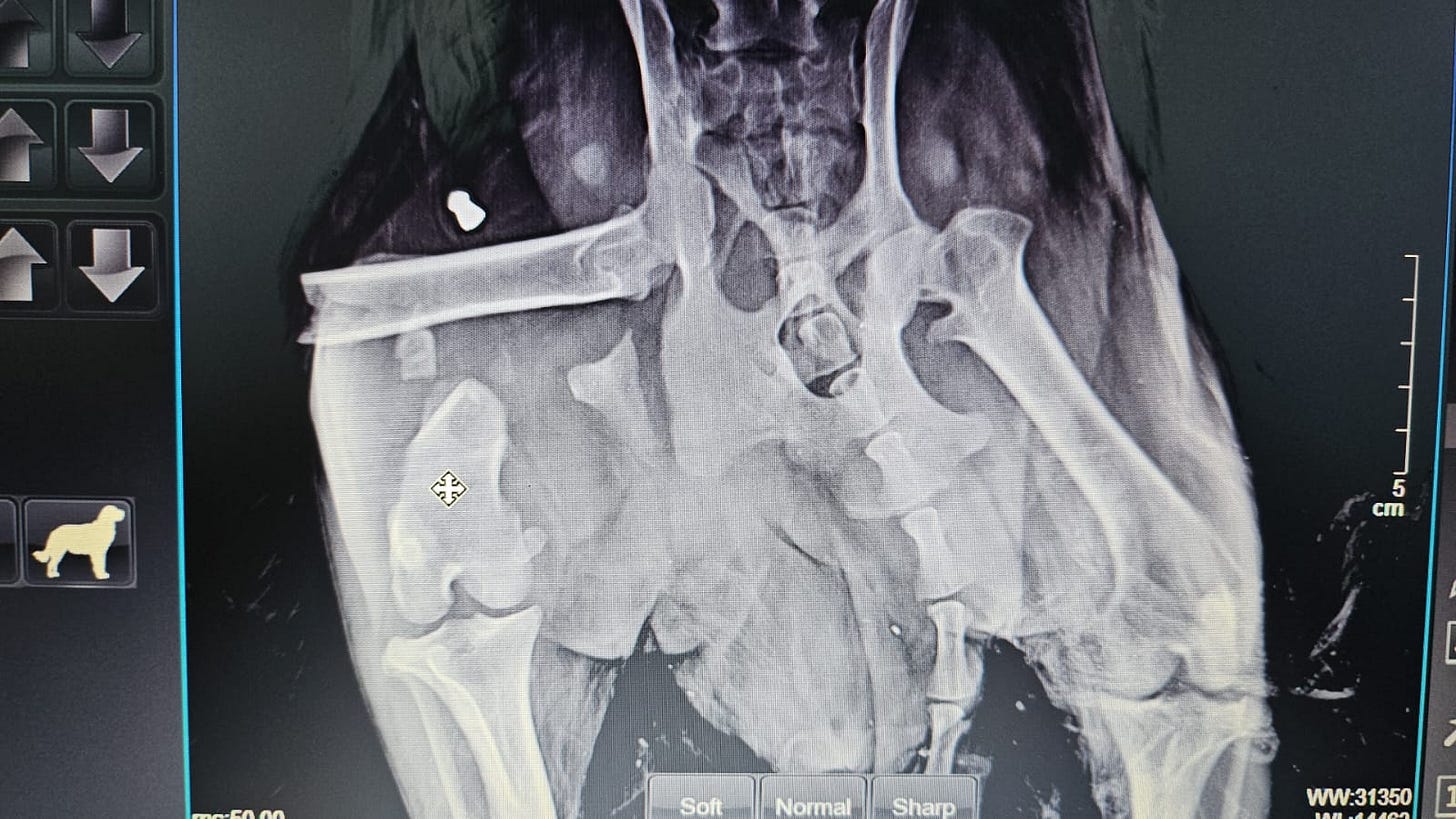

An X-ray revealed that Pepper's leg was broken and her pelvis fractured.